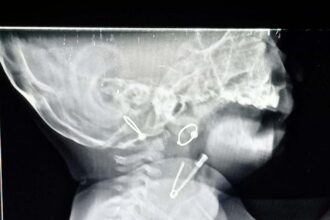

घशामध्ये अडकलेली सेफ्टी पिन काढण्यात वालावलकर रुग्णालयाच्या डॉक्टरांना यश